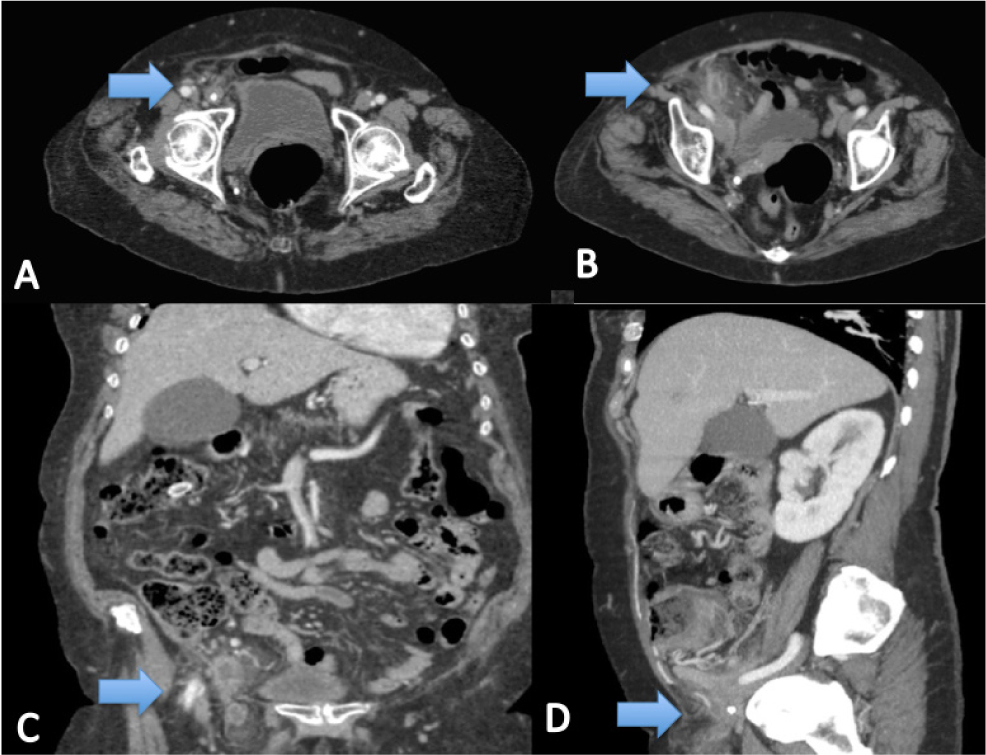

A 77-year-old female was referred to the emergency department with diarrhea, vomiting and diffuse abdominal pain for two days. Her past medical history included hypertension, type 2 diabetes mellitus, dyslipemia, bronchial asthma, irritable bowel syndrome and hypothyroidism. On admission, the patient was haemodynamically stable and afebrile. Physical findings revealed a soft, non-distended abdomen with a tender mass in the right inguinal region measuring approximately 4x6cm. Laboratory tests showed a white blood cell count 12.30 x103/mm3, with 90.9% neutrophils, and CRP 2 mg/L. X- ray did not reveal bowel obstruction. A CT showed edematous appendix with an appendicolith inside it, in a right femoral hernia sac. The decision was taken to perform laparoscopic surgery. The patient received 2g/200mg of amoxicillin/clavulanic acid i.v. preoperatively. With general anaesthesia, an infraumbilical incision was made, and a pneumoperitoneum was obtained using Hasson’s open technique. A 5-mm abdominal port was placed suprapubically and a 12-mm port in the left iliac fossa. A 10-mm, 30-degree telescope was used to examine the abdominal cavity. A large portion of the appendix, which had undergone necrosis and perforated, was seen to pass through the femoral defect from where purulent fluid was evacuated. The mesoappendix was stapled and transected with a tissue sealing generator, and the base of the appendix with a linear cutter stapler. The femoral defect was repaired primarily with an absorbable suture. Post-operative recovery was uneventful and the patient was discharged on the sixth postoperative day. Histology showed acute ischaemic and necrotic appendicitis with perforation. During eight months of follow-up, the patient has not experienced complications.

A, B, C, D Case Report 2. CT images Arrow: Appendix